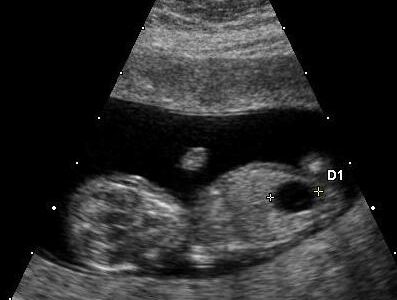

Fetal Megacystis: What Does It Indicate and How Is It Managed?

Every ultrasound scan during pregnancy brings both anticipation and reassurance to expectant parents. Every mom-to-be